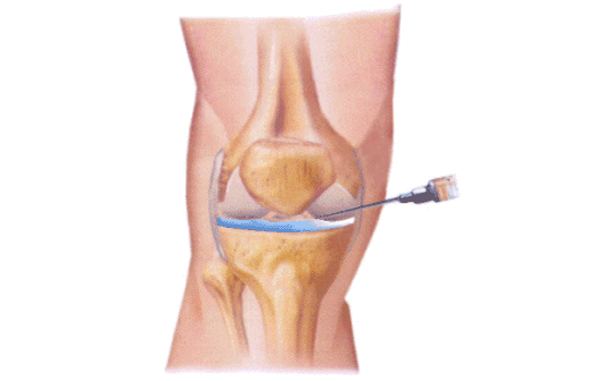

La Viscosuplementación es el procedimiento por el cual se aplica en forma intraarticular (cadera, rodilla, tobillo, mano, etc.) Ácido Hialurónico como tratamiento en las patologías que afectan al cartílago (artrosis, osteocondritis, posquirúrgicos) disminuyendo la fricción o el roce articular, con el consecuente alivio del dolor, y lo que es más importante, evitando el deterioro articular con el paso del tiempo.